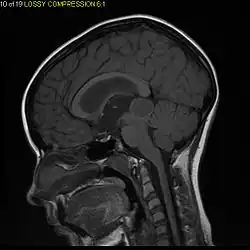

Pilocytic astrocytoma (and its variant pilomyxoid astrocytoma) is a brain tumor that occurs most commonly in children and young adults (in the first 20 years of life). They usually arise in the cerebellum, near the brainstem, in the hypothalamic region, or the optic chiasm, but they may occur in any area where astrocytes are present, including the cerebral hemispheres and the spinal cord. These tumors are usually slow growing and benign, corresponding to WHO malignancy grade 1.[1]

Usually – depending on the interview of the patient and after a clinical exam which includes a neurological exam and an ophthalmological exam – a CT scan and/or an MRI scan will be performed to confirm the presence of a tumor. They are usually easily distinguishable from normal brain structures using these imaging techniques. A special dye may be injected into a vein before these scans to provide contrast and make tumors easier to identify. Pilocytic astrocytomas are typically clearly visible on such scans, but it is often difficult to say based on imaging alone what type of tumor is present.